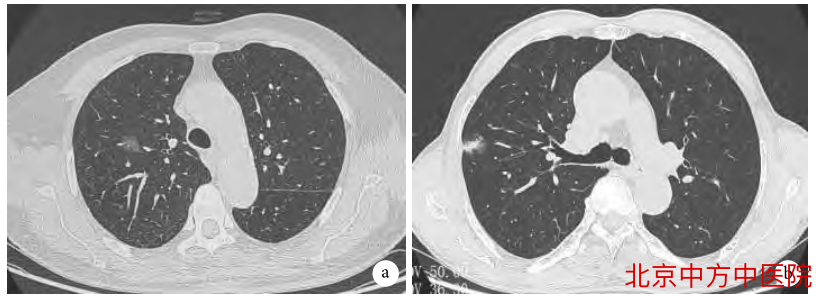

a:纯磨玻璃结节;b:混合磨玻璃结节

目前,根据CT肺窗上是否存在实性成分,可将其分为纯磨玻璃结节(pGGN)和混杂性磨玻璃结节(mGGN)。

其中,pGGN又称为非实性结节,其内不含有实质成分;mGGN又称为部分实性结节,其内既有纯磨玻璃密度影,又含有实质成分。